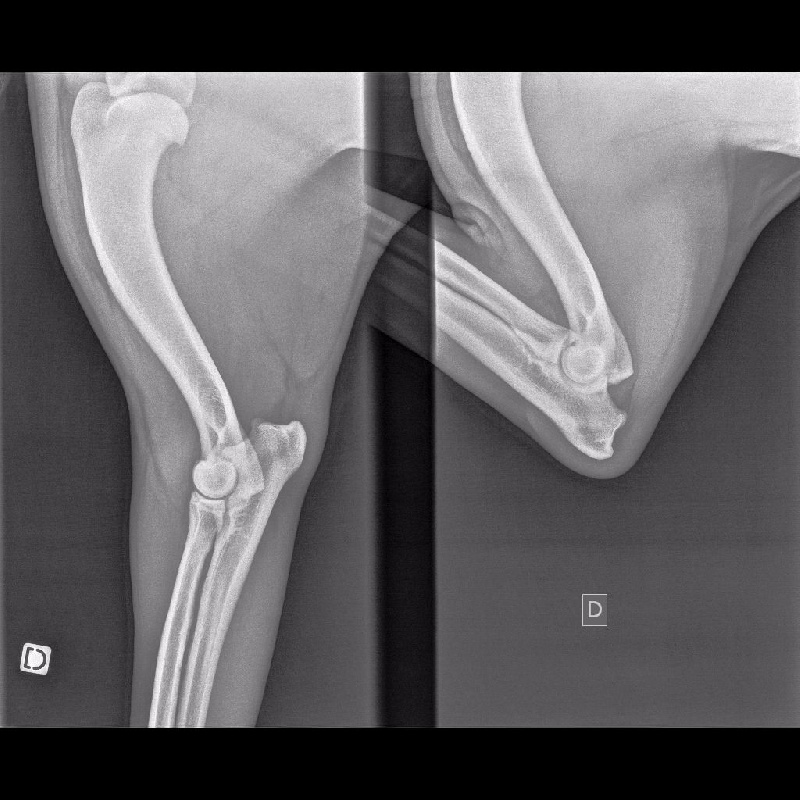

COUDES